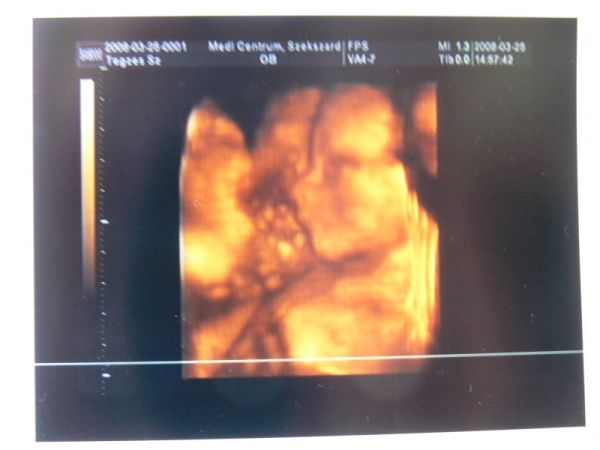

Ki mondta,hogy Szexárdon fog szülni?Mert én is...Ma beszéltem a dokival,elvállalt.Jövő héten megyek hozzá,nagyon normálisnak tűnt a telefonban.Csináltatok mindjárt egy 4D-t is,hogy láthassa a család a törpöket! :wink:

2 hét múlva megyek 4d-re én is, de nem a kórházba, hanem a Medicentrumba... kicsit drágább, de állítólag jobb is.. meglátjuk...

Én is a Medibe megyek,mert ott a dokim:dr. Imre József.Valamint láttam,hogy nekik van ikerfejes NST-jük,ami nekem nem hátrány... :lol: :lol: :lol:

Augusztus 1-re vagyunk kiírva, és múlt héten voltunk 4D-n, biztos hogy a kislányok csapatát fogjuk erősíteni, bár a névben nem vagyunk még biztosak. Kettő között vacilálunk a Csenge és a Virág között. Tegnapig még a Jázmin is szerepelt, de amikor láttam, hogy ilyen sok van, kihúztuk a listánkról :D